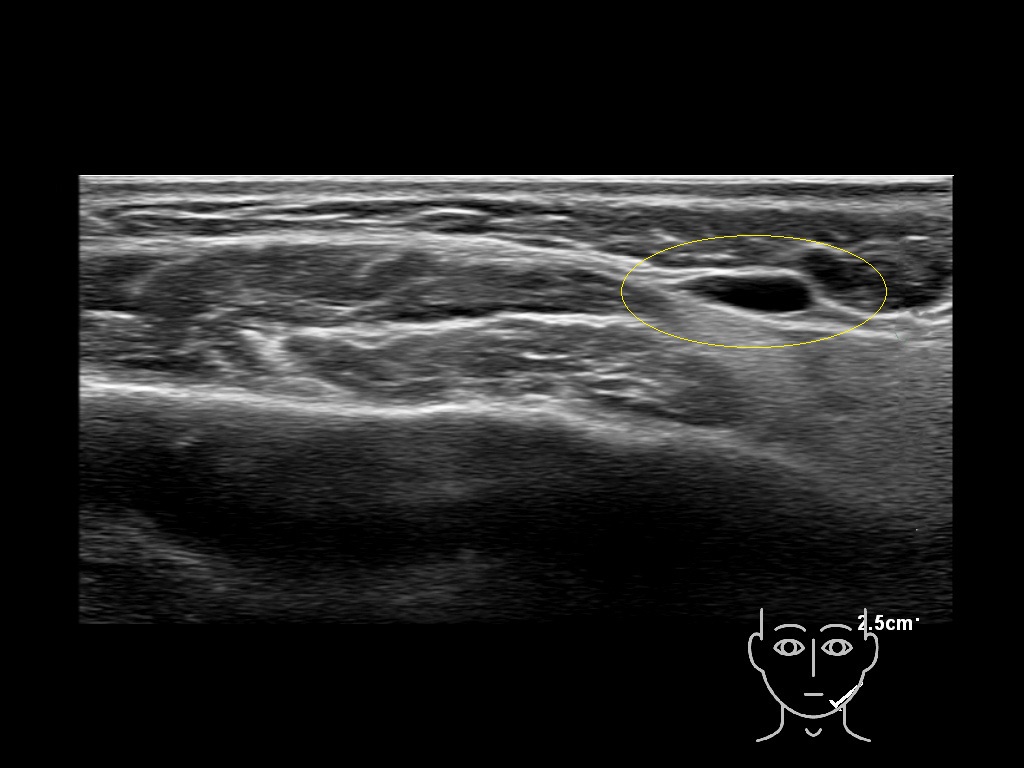

Study the first image to recognize the different layers. If you are sure about the layers, swipe to the second image to view the answer (if applicable).